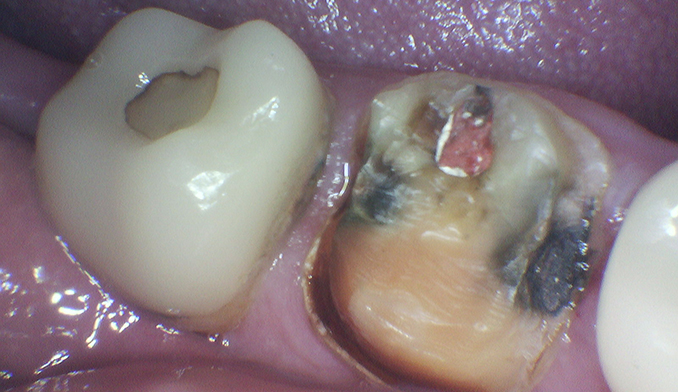

Molar Extraction, Bone Grafting, and Implant Placement

The patient’s lower right molar was severely damaged and could not be saved. After removing the tooth, we performed bone grafting to preserve the bone structure, ensuring a strong foundation for future treatment. Four months later, after proper healing, a dental implant was placed to restore function and maintain jaw health.